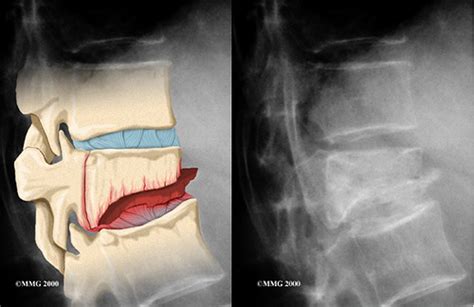

Перелом позвоночника: виды по типу и отделу, си...

Компрессионные переломы позвоночника. Клиника -...

Лечение компрессионного перелома позвоночника -...